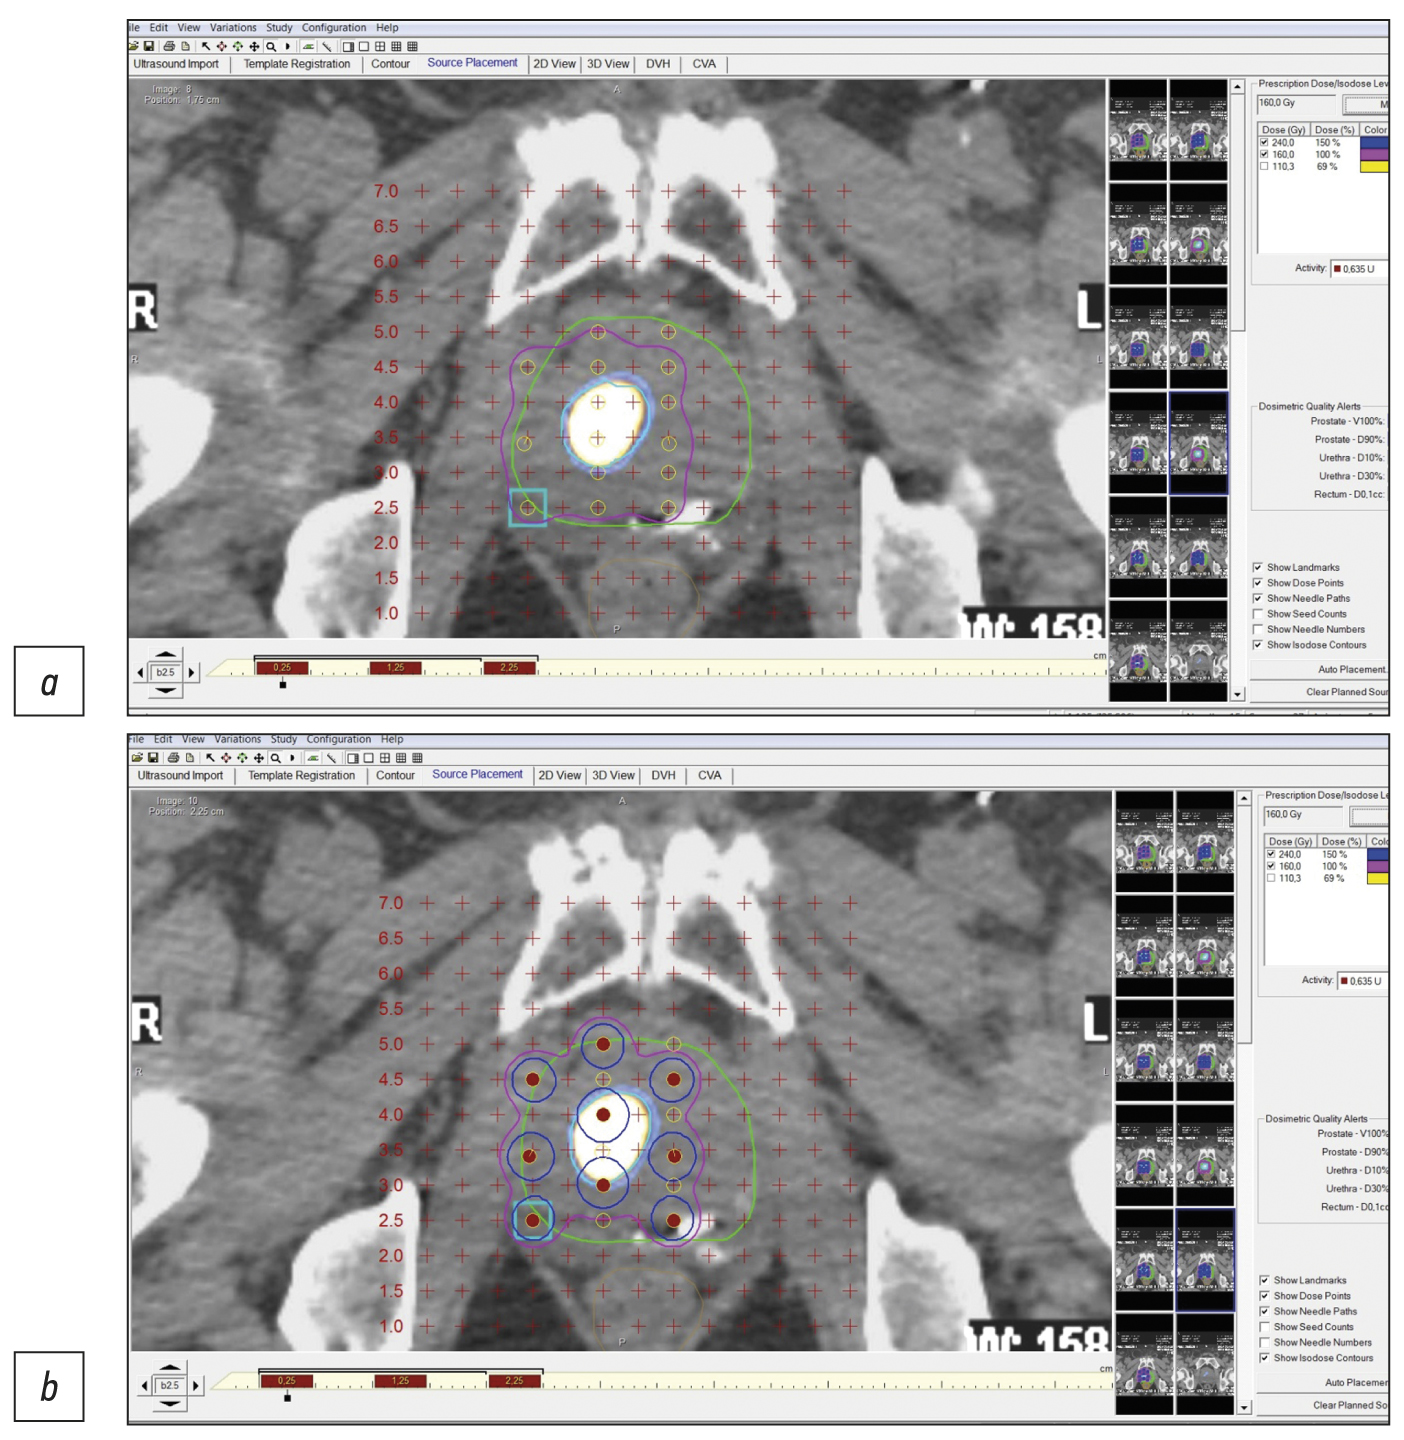

Precision low-dose brachytherapy of prostate cancer under PSMA-receptor molecular visualization

Abstract

Brachytherapy with implantation of micro sources based on isotope 125I is a preferred treatment for localized prostate cancer without signs of germination of the gland capsule and in the absence of signs of metastases (stage cT1-T23aN0M0). Structural imaging methods (ultrasound, computed tomography, and magnetic resonance imaging) do not have high specificity in the differential diagnosis of prostate cancer. Hybrid technologies of radiation imaging (single-photon emission computed tomography/computed tomography, positron emission tomography/computed tomography, and positron emission tomography/magnetic resonance imaging) combine the advantages of high sensitivity of cross-sectional structural imaging methods (computed tomography and magnetic resonance imaging) and high specificity of molecular imaging methods (single-photon emission computed tomography and positron emission tomography) with tumorotropic radiopharmaceuticals. In this original clinical study, based on seven observations of localized prostate cancer (Gleason 6–7), it was shown that the precision of low-dose brachytherapy using 125I micro sources of localized prostate carcinomas, along with targeted biopsy, can be increased using hybrid methods of PSMA-receptor molecular imaging (single-photon emission computed tomography/ computed tomography, positron emission tomography/ computed tomography). The single-photon emission computed tomography/ computed tomography method is more accessible than positron emission tomography/ computed tomography. Moreover, when coupled with cold kits (HYNIC-PSMA), it allows research within any radioisotope diagnostics laboratory equipped with single-photon emission computed tomography/ computed tomography. The innovative technology of PSMA-navigation biopsy and brachytherapy, under the control of hybrid molecular imaging, can be used in primary and recurrent cases of localized prostate cancer, increases the accuracy and reduces the traumatic nature of procedures, and increases the medical and economic efficiency of low-dose brachytherapy with 125I micro sources. Further research is needed to improve the technology and evaluate its long-term results.